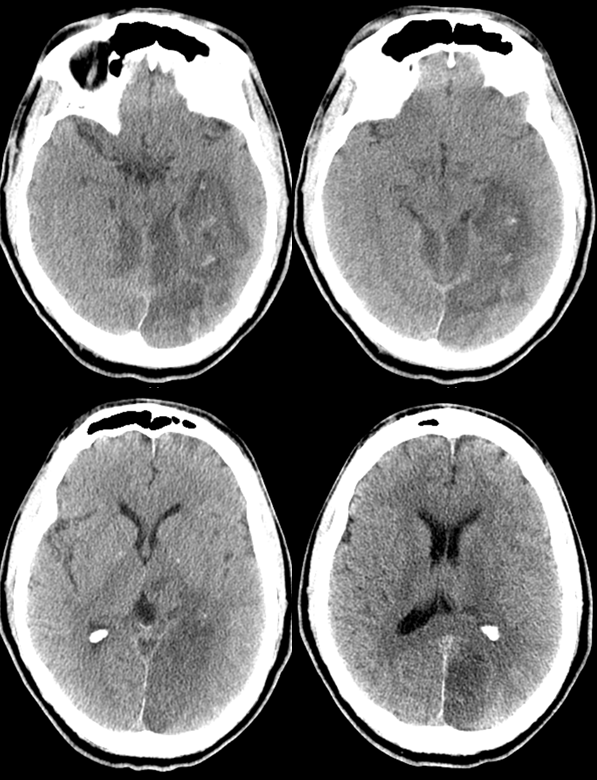

From www.researchgate.net

Recurrent strokes and fetaltype PCA in our patient. (A, B) Right What Is A Pca Stroke This article provides an overview of pca stroke and focuses exclusively on stroke of arterial origin involving the pca territory (see the images below). Posterior cerebral artery (pca) infarcts arise, as the name says, from occlusion of the posterior cerebral artery. Posterior circulation ischaemic stroke is a clinical syndrome associated with ischaemia related to stenosis, in situ thrombosis,. A solid. What Is A Pca Stroke.

From www.cureus.com

Cureus Massive Left Ventricular Thrombus Causing Bilateral Posterior What Is A Pca Stroke Approximately 795,000 people have strokes every year in the us (cdc) posterior circulation strokes account for. Posterior cerebral artery (pca) infarcts arise, as the name says, from occlusion of the posterior cerebral artery. A solid understanding of the pathophysiology of a posterior cerebral artery (pca) stroke as well as the syndrome relating to it, requires adequate. This article provides an. What Is A Pca Stroke.

Cureus A Rare Presentation of Posterior Cerebral Artery Stroke With What Is A Pca Stroke Posterior cerebral artery (pca) infarcts arise, as the name says, from occlusion of the posterior cerebral artery. This article provides an overview of pca stroke and focuses exclusively on stroke of arterial origin involving the pca territory (see the images below). Posterior cerebral artery (pca) stroke is a type of ischemic stroke that occurs when there is a blockage or. What Is A Pca Stroke.